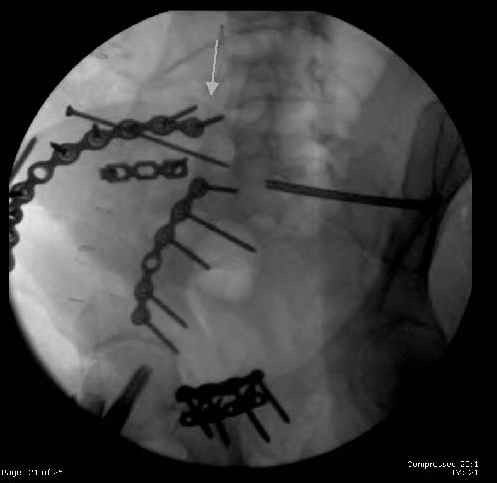

Here are the postop fluoros.

First exposed symphysis & clamped w/Faraboeuf as close to anatomic as possible.

Then extended to R ilioinguinal,really just the lateral window.

Reduced the triangular wedge piece of iliac wing to posterior intact ilium (crescent), held w/k-wire, then used 3-hole push plate to keep from moving, lagged from lat-med w 3.5 screw.

Then 6-hole plate along brim with 1 screw in R sacral ala. Then lagged 2 screws along crest A --> P. finally 10-hole plate along inner aspect of crest. R posterior ilium still a bit stepped off.

Symphysis then 'fine-tuned' & reduced as close as possible to anatomic (but, still with forward rotation of R hemipelvis - or, is it extension?) Accepted that amount of deformity and plated symph

with 4-hole symphyseal plate.

Fluoroed L SI joint and it seemed stable, but wide. So, applied c-clamp to try to squeeze down L SI joint (and note, on the last slide attached, that it's still wide), and got it closer. Single perc Iliosacral screw 40mm thread.

Applied second plate anteriorly on symphysis as I wasn't confident L SI was as stable as it could be and wanted to protect it better.

The mal-alignment that you indicated by the arrow in your photo of the ilium, do you have some idea as to how that occurred? was the crescent component locked in such a manner that it could not be moved?